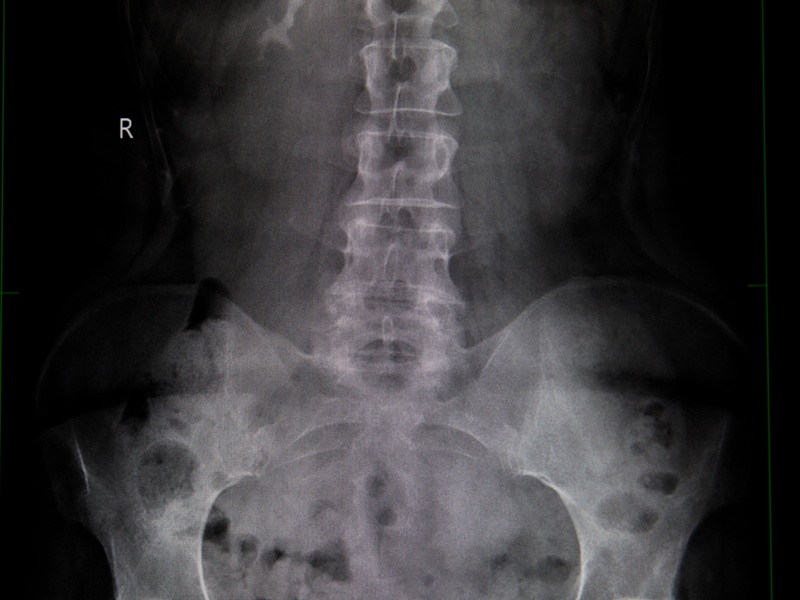

Цифровой рентген таза — это метод лучевой диагностики. Медицинская визуализация позволяет получить изображение костных структур таза: тазовых костей, крестца, копчика, головок и вертлужных впадин бедренных костей. Снимки дают врачу возможность увидеть даже минимальные изменения в костной ткани, наличие травм, дегенеративных процессов или аномалий развития.

Что показывает рентген таза

Рентгенография тазовых костей — это диагностика переломов, трещин костей после падений и травм таза. Также метод позволяет:

- оценить состояние при артрозе или дисплазии тазобедренных суставов;

- выявить врожденные или приобретенные деформации, включая возрастные изменения тазовых костей;

- увидеть признаки воспалительных и дегенеративных процессов, например остеоартрита;

- контролировать эффективность лечения (также проводится послеоперационная диагностика);

- оценить симметрию суставов и положение тазобедренных костей у детей.

Рентген малого таза у женщин применяется для исключения аномалий строения таза или на этапе подготовки к родам. В травматологии — для подтверждения повреждений. В педиатрии — для своевременной диагностики дисплазии.